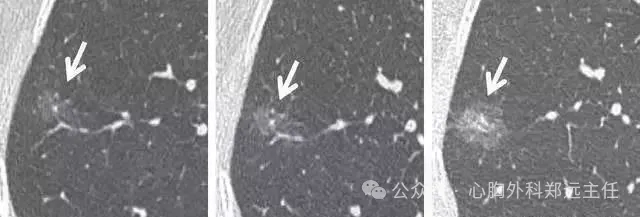

横看成岭侧成峰,下图CT扫描时显示的是叶间裂上的一个结节影(图1),而CT冠状面重建则显示该结节影其实为线状的疤痕或淋巴组织(图2)。